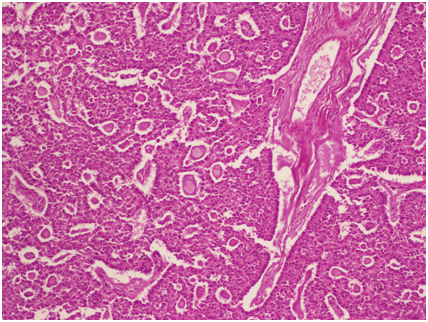

Five years later, she presented with abdominal pain. Computed tomography scan shows a 75 mm right adnexal mass evoking a cystic recurrence (Figure 2). The serum rate of anti-müllerian hormone (AMH) was elevated and measured 325 ng/ml. CA-125 rates were less than 35 UI/ml. In order to investigate PJS, a colonoscopy was performed and showed recto-colic polyposis. Mammogram showed benign cystic lesion of the breast. Papa smear did not show any abnormal cells. Radical surgery was recommended but the patient refused because of her will of childbearing. Laparoscopic exploration found a right adnexal cystic mass (Figure 3), with no evidence of ascites or peritoneal carcinosis. We underwent a cystectomy; leaving an ovarian tissue. The histologic findings showed circumscribed columnar epithelial nests composed of ring shaped tubules, which are encircled by hyalinized basement membrane-like material and concluded for a recurrent SCTAT. No mitotic count was reported (Figure 4) and (Figure 5). One month after surgery, hormonal rates were measured after ovarian stimulation and did not show hormonal activity. Fertility preservation attempt was a failure and the patient is proposed for a complementary surgery.

Figure 5: Sex cord stromal tumor with annular tubules of the ovary (H&E stain, x200).